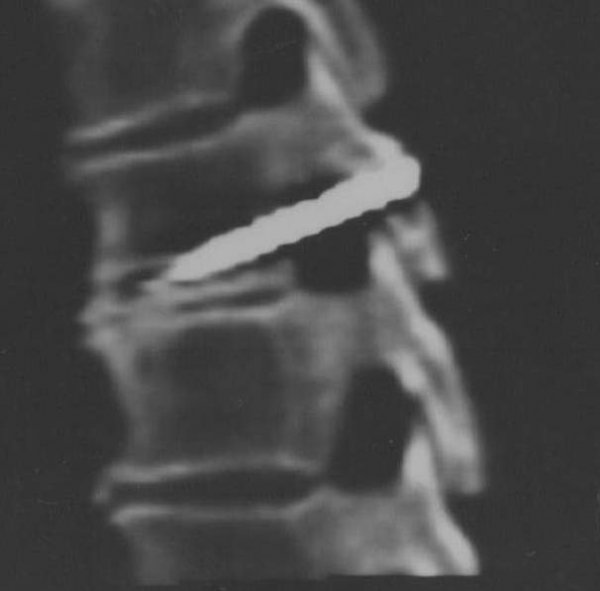

1. В прошлом году известный питерский специалист по исследованию аномальных явлений кандидат технических наук Сергей Кузионов поделился интересными фактами и наблюдениями. В частности, после 23-ей минуты видеосюжета он рассказал, что работал в США консультантом по последствиям "инопланетных" операций на землянах. На времени 44:25 Сергей говорит о церковных чудесах, в том числе поновлении икон в Питере. Мне лично пришлось исследовать случай ксеноимплантата в позвонок живого человека. Этот человек жив-здоров. Он поэт, композитор, бард - Андрей Школин. Подробности о том, что у него содержится аномального в пятом грудном позвонке в моей статье https://news.vtomske.ru/details/25919-s-shurupom-v-pozvonke-foto Мне интересно знать, фиксировались ли подобные имплантаты в тело людей в Беларуси?